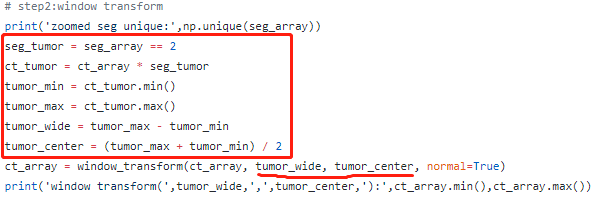

代码

#by tumor (recommended)

tumor_wide = tumor_max - tumor_min

tumor_center = (tumor_max + tumor_min) / 2

tumor_wl = window_transform(ct_array, tumor_wide, tumor_center, normal=True)

saved_name = os.path.join(saved_path, 'tumor_wl_1.nii')

saved_preprocessed(tumor_wl, origin, direction, xyz_thickness, saved_name)